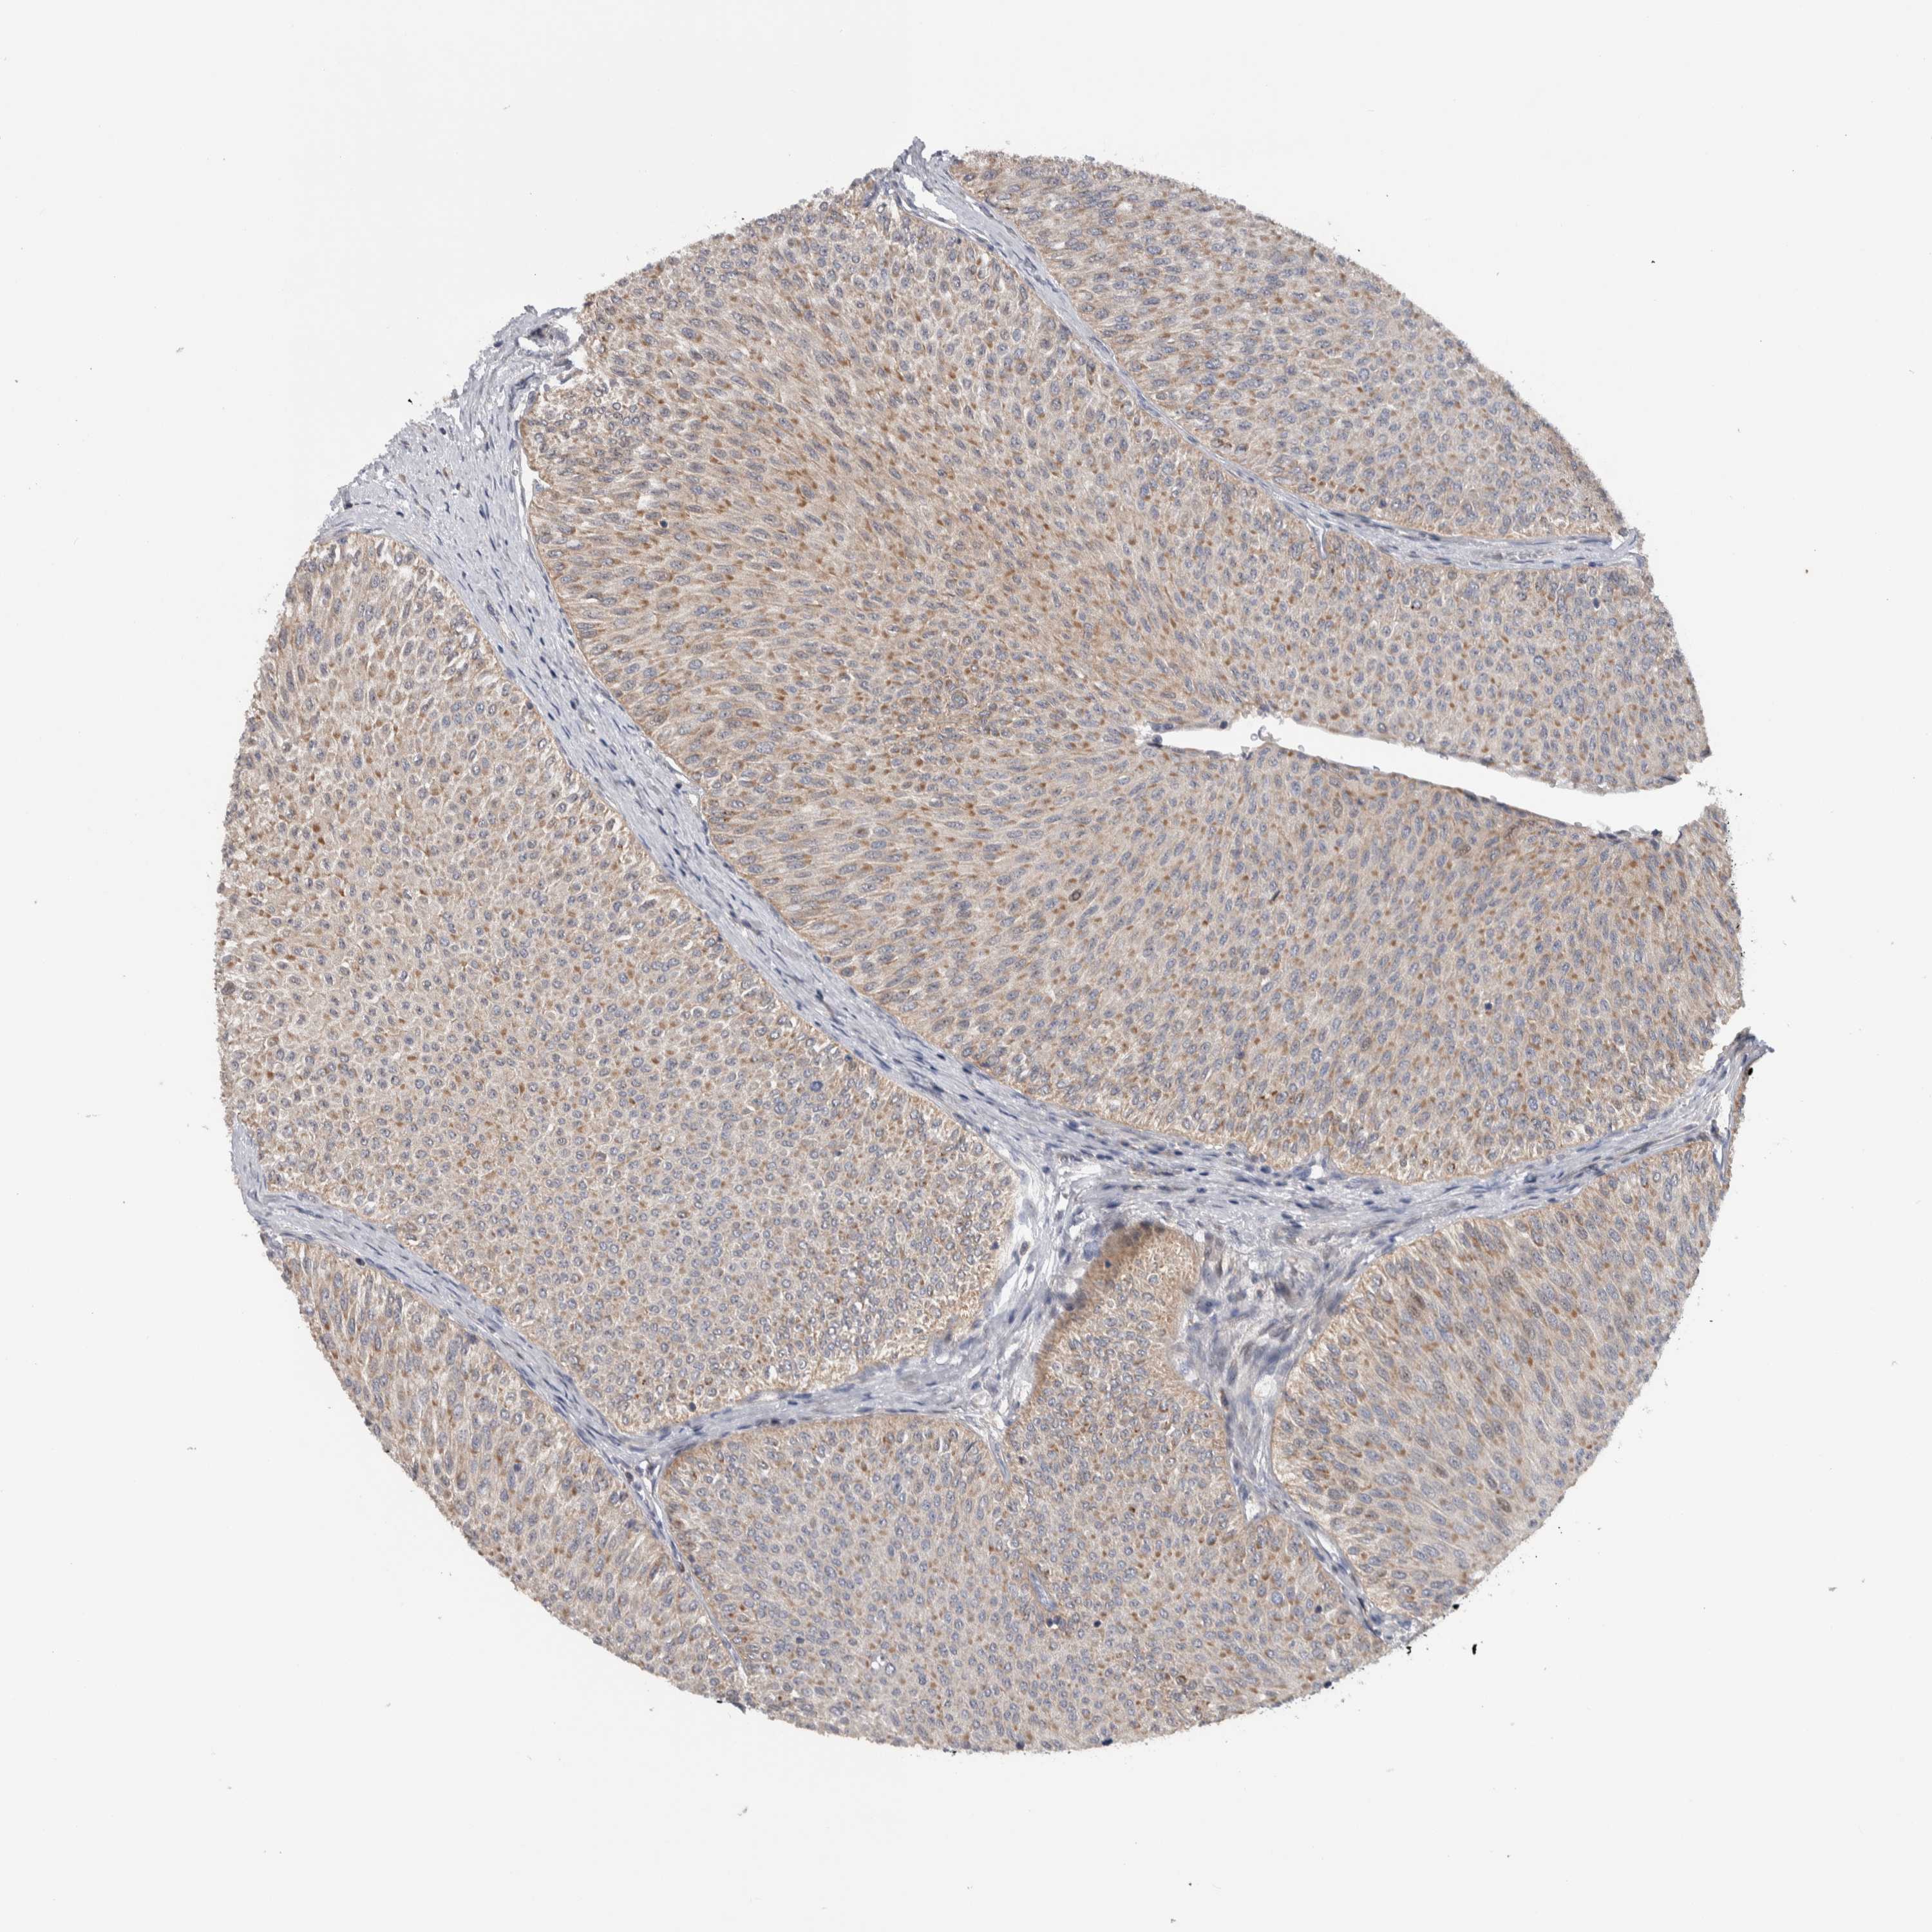

UROTHELIAL CANCER - Protein expressioni

A mouse-over function shows sample information and annotation data. Click on an image to view it in a full screen mode. Samples can be filtered based on level of antibody staining by selecting one or several of the following categories: high, medium, low and not detected. The assay and annotation is described here.

Note that samples used for immunohistochemistry by the Human Protein Atlas do not correspond to samples in the TCGA dataset.

Antibody stainingi

Antibody staining in the annotated cell types in the current human tissue is reported as not detected, low, medium, or high, based on conventional immunohistochemistry profiling in selected tissues. This score is based on the combination of the staining intensity and fraction of stained cells.

Each image is clickable and will lead to virtual microscopy that enables deeper exploration of all samples and also displays staining intensity scores, fraction scores and subcellular localization as well as patient and tissue information for each sample.

Antibody HPA009040

Antibody HPA024566

Staining

High

Medium

Low

Not detected

Intensity

Strong

Moderate

Weak

Negative

Quantity

>75%

75%-25%

<25%

None

Location

Nuclear

Cytoplasmic/membranous

Cytoplasmic/membranous,nuclear

Urothelial carcinoma, Low grade